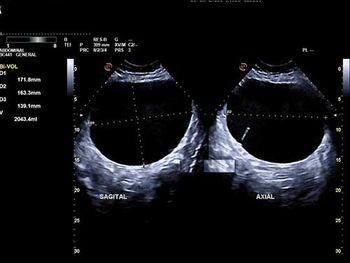

Challenge your diagnostic skills: What's the diagnosis and prognosis based on these images of the fetal brain in a third trimester pregnancy?